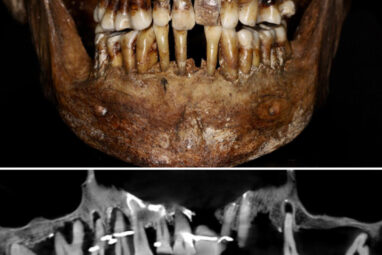

Scientists have discovered the long-buried secret of a 17th-century French aristocrat 400 years after her death: she was using gold...